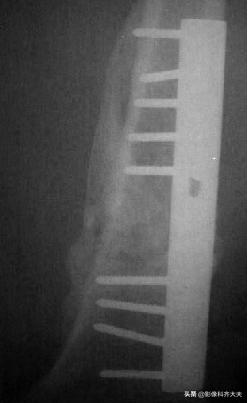

炎症消退期:2-3周,骨折线模糊

骨痂出现阶段:3-4周,骨痂“托”

骨痂连接阶段:4-6周,骨痂连接成桥

骨痂成熟阶段: 6-8周,看不到骨缝

骨痂塑形阶段:骨变形逐渐矫正

骨折愈合的证据:大量骨痂和骨小梁穿越骨折处。

肱骨远端骨折后大量骨痂形成,骨小梁穿越骨折处